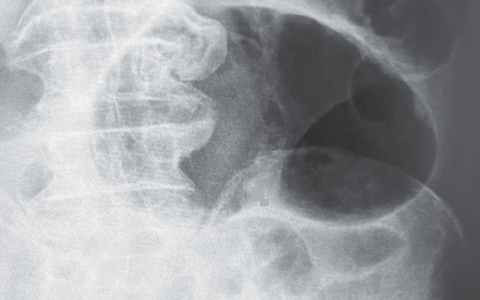

A 4-year-old boy with a history of mental retardation and seizures is brought to the physician with a three-month history of worsening shortness of breath. During physical examination, the physician notices numerous acne-like papules on the patient’s face. Echocardiography shows significant left ventricular outflow obstruction. Which of the following is the most likely diagnosis for this patient’s heart condition?

一名有精神发育迟滞和癫痫病史的4岁男孩因呼吸急促恶化3个月就诊。体格检查时,医师注意到患者脸上有许多痤疮样丘疹。超声心动图显示明显的左心室流出道梗阻。下列哪项是该患者心脏状况最有可能的诊断?

结节性硬化症是一种以多核非典型星形胶质细胞结节性增生为特征的遗传疾病(常染色体显性)。这些形成的管子遍布大脑皮层和脑室周围区域。经典三联征仅在最严重的病例中表现,包括癫痫发作、智力障碍和面部血管纤维瘤(也称为皮脂腺瘤)。一半的结节性硬化症患者发展为横纹肌瘤,这是原发性心肌肿瘤,虽然是良性的,但可能损害心脏功能,特别是房室瓣。结节性硬化症也与肾血管平滑肌脂肪瘤有关。

正确答案:D